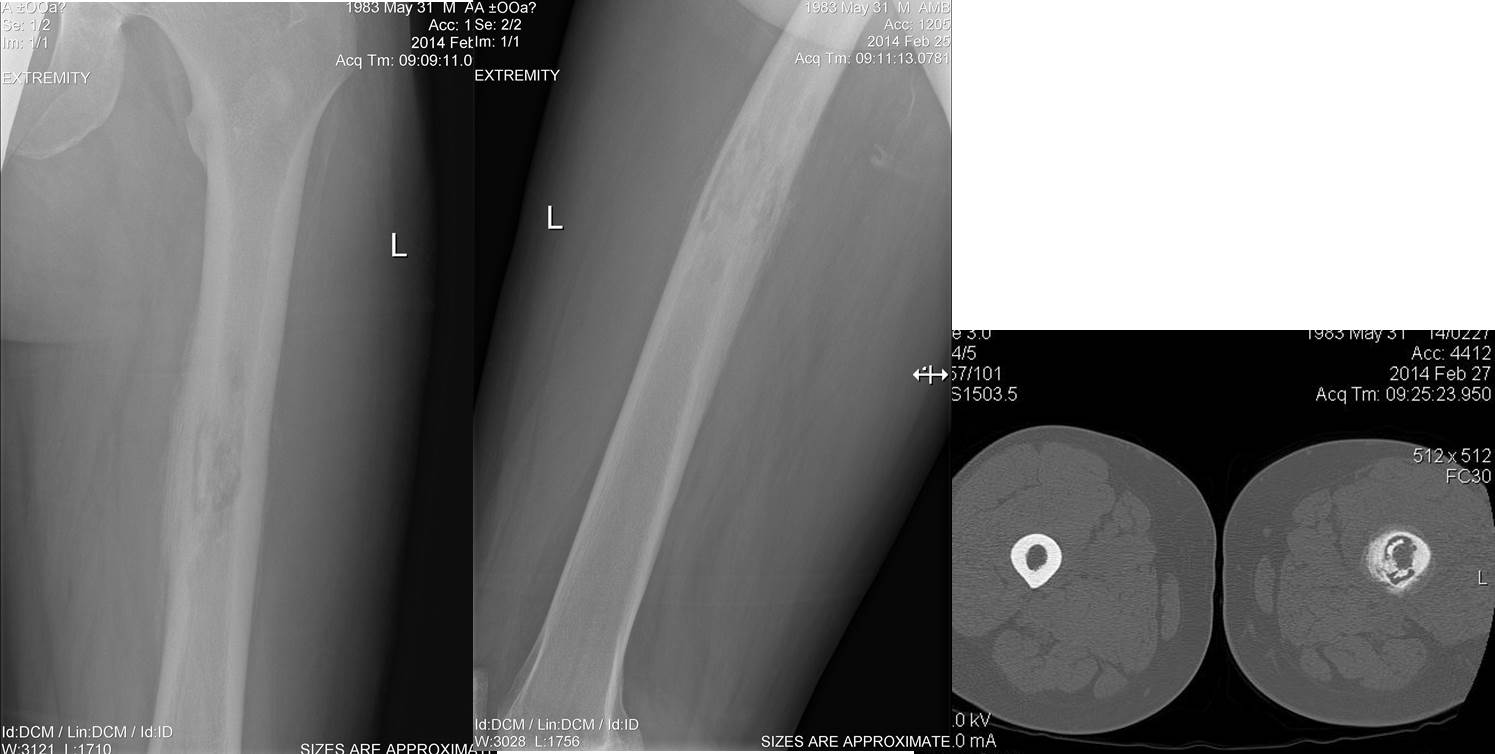

Уважаемые коллеги, помогите разобраться, пожалуйста. Мужчина 31 года от роду, ростом 200 см и весом 120 кг, переболел около 3-х месяцев назад каким-то загадочным "некротизирующим фасциитом" левого бедра.

Лихорадил высоко, в крови - картина микробного воспаления. Лечили активно, разрезами по типу лампасных, антибиотиками... Высевался почему-то эпидермальный стафилококк. На тот момент изменений бедренной кости ни на рентгене, ни на КТ не было. Сейчас вот такая картина на КТ. Бедро не болит, пока ходит на костылях. Отека, гиперемии нет. Температура тела нормальная. Лейкоцитоза нет, сдвига нет. С остеомиелитами часто не сталкиваемся... Хотелось бы узнать мнение уважаемого Форума...

На рентгенограммах картина гематогенного остеомиелита с двумя, как минимум, формирующимися секвестрами. В настоящее время у пациента стадия нестойкой ремиссии. Я бы рекомендовал выполнить фиксацию бедра гипосовой повязкой (ортезом)с рентгенологическим контролем через 2 месяца, охранительный режим минимум на 1 год. При обострении - хирургическая обработка гнойного очага с удалением секвестров, пластикой остеозамещающими препаратами.

То, что здесь остеомиелит согласен.

3. А вот что нет остеосаркомы я полностью не уверен. Какая то странная периостальная реакция..

добрый день!недавно был схожий случай у молодого человека 19 лет.Шли на секвестрэктомию,смутила очень плотная,темно-багровая надкостница.При гистологии-саркома!Мне кажется в данном случае онконастороженность не помешает!